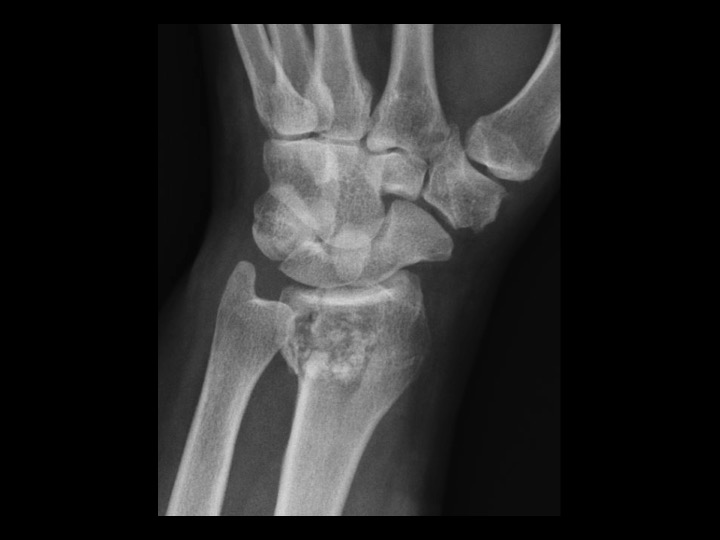

57F fell 2 weeks ago

Solitary epiphyseal enchondroma is reportedly rare (in the attached article, the incidence is 4%, higher than other series). This came to attention because of fracture after fall, though I would characterize this as a pathologic fracture, since the lesion occupies most of the DR with endosteal scalloping. In the attached article, there was no aggressive behavior on limited follow up. The radiographic appearance is non-aggressive. Is that sufficient to assume this is an epiphyseal enchondroma, not requiring close and continued imaging follow up? Or does the epiphyseal location raise suspicion and require continued surveillance after the fracture has healed? I imagine this might require currettage and grafting, at which time there would be pathology...but this is being followed currently.

enchondroma ( RID4128 )